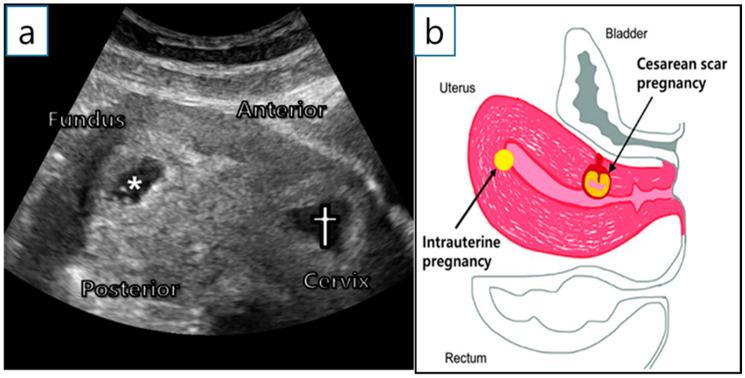

Heterotopic cesarean scar pregnancy (HCSP) is a combination of cesarean scar pregnancy (CSP) and intrauterine pregnancy (IUP). Cesarean scar pregnancy is accompanied by life-threatening complications, such as uterine rupture and massive bleeding. Herein, we present a case of HCSP treated with selective potassium chloride injection into the CSP under ultrasonography in association with uterine cerclage to control vaginal bleeding; this led to a successful IUP preservation and full-term delivery. Additionally, we will review several previous reports on HCSP management, including our case.

剖宫产瘢痕部位异位妊娠(HCSP)是剖宫产瘢痕妊娠(CSP)与宫内妊娠(IUP)的合并情况。剖宫产瘢痕妊娠伴有危及生命的并发症,如子宫破裂和大出血。在此,我们报告1例HCSP患者,在超声引导下向CSP部位选择性注射氯化钾并联合子宫环扎术以控制阴道出血,成功保留了IUP并实现足月分娩。此外,我们将回顾既往关于HCSP治疗的几份报告,包括我们的病例。